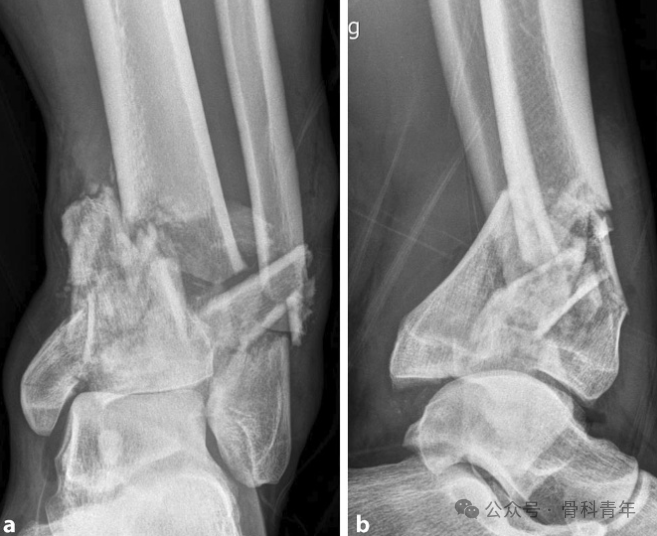

固定(Span):实施跨关节外固定架固定术;